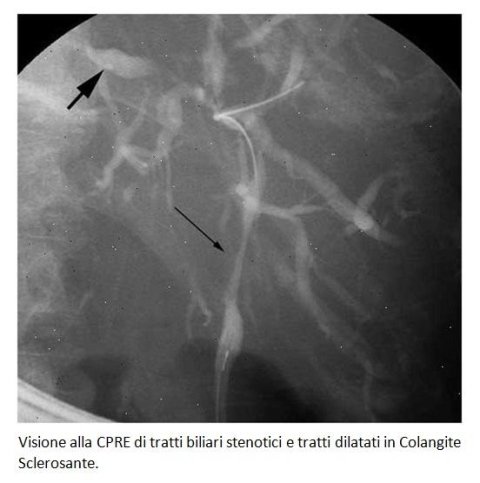

Colangite sclerosante. Se refiere a una hinchazón (inflamación), cicatrización y destrucción de las vías biliares dentro y fuera del hígado. Colangite Sclerosante Primitiva F Rosina Presidio Sanitario Gradenigo Torino F Rosina Presidio Sanitario Gradenigo Torino Primary Sclerosing CholangitisPrimary Sclerosing Cholangitis an immunemediated inflammatory chronic cholestatic liver disease characterized by. Colangite sclerosante secondaria quando consegue ad una malattia sottostante clinicamente identificabile → tra le principali cause di colangite sclerosante secondaria si ricordano la presenza di calcoli all'interno dei dotti biliari, la pancreatite ricorrente, gli interventi chirurgici sull'albero biliare, l'AIDS o l'iniezione di farmaci chemioterapici attraverso l'arteria epatica.

2) Colangite sclerosante E' più frequente nell'uomo tra i e i 40 a Si associa frequentemente a malattia infiammatoria intestinale Sono presenti ANCA Per fare la diagnosi bisogna escludere calcolosi biliare, precedente chirurgia sulle vie biliari, anomalie biliari congenite, cirrosi biliare, colangiocarcinoma 3) Epatite cronica autoimmune. Morelli A, Narducci F, Pelli MA, Ciccone R, Rossi L, Gubbiotti A La colangiografia retrograda per via transendoscopica nella diagnosi della colangite sclerosante primitiva Osservazione di sei casi Minerva Med 1978 Oct 31;. Colangite sclerosante primitiva By Giorgio Maria, Gaia Marniga, Federica Cadeddu, Casimiro Nigro, Pasquale Mazzeo, Serafino Vanella and Giuseppe Brisinda Topics Colangite sclerosante, Settore MED/12 GASTROENTEROLOGIA.

La colangite sclerosante primitiva è sospettata in pazienti con anomalie inspiegabili nei test di funzionalità epatica, in particolare in quelli con associata una malattia infiammatoria intestinale cronica Un quadro colestatico è tipico, con aumento della fosfatasi alcalina e della gammaglutamil transpeptidasi piuttosto che delle aminotransferasi. Colangite sclerosante primaria è una malattia del fegato che provoca l'infiammazione delle vie biliari, causando loro di diventare bloccato Bile, che è fatto dal fegato, viene memorizzato dalla cistifellea e rilasciato durante la digestione per contribuire ad abbattere i grassi. Primary colangite sclerosanteSecondary colangite sclerosanteRecurrent Pyogenic Colangite Alcune delle domande chiave a cui si risponde in questo rapporto – Panoramica dettagliata delle dimensioni del mercato colangite – Studio qualitativo del mercato in termini di tecnologia, aree di ricerca e nuovi sviluppi.

Primary sclerosing cholangitis (PSC) is an uncommon inflammatory condition, which affects the biliary tree resulting in multiple strictures, liver damage, and eventually cirrhosis The diagnosis can be made when there are classical imaging features in the correct clinical context, and secondary causes of cholangitis have been excluded 16. Si associa di frequente con malattie infiammatorie intestinali che va sempre ricercata, specie RCU, raramente Crohn.